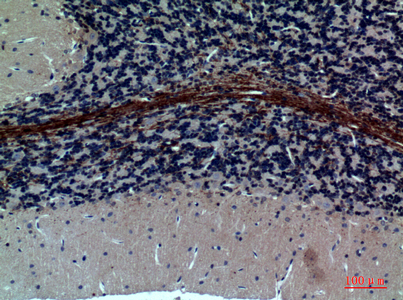

![GABA A Receptor alpha 1 antibody [N1C1] detects GABA A Receptor alpha 1 protein at cytoplasm in rat brain by immunohistochemical analysis. Sample: Paraffin-embedded rat brain. GABA A Receptor alpha 1 antibody [N1C1] (GTX104027) diluted at 1:500.

Antigen Retrieval: Citrate buffer, pH 6.0, 15 min](https://www.genetex.com/upload/website/prouct_img/normal/GTX104027/GTX104027_39925_20160309_IHC-P_R_w_23060120_899.webp)